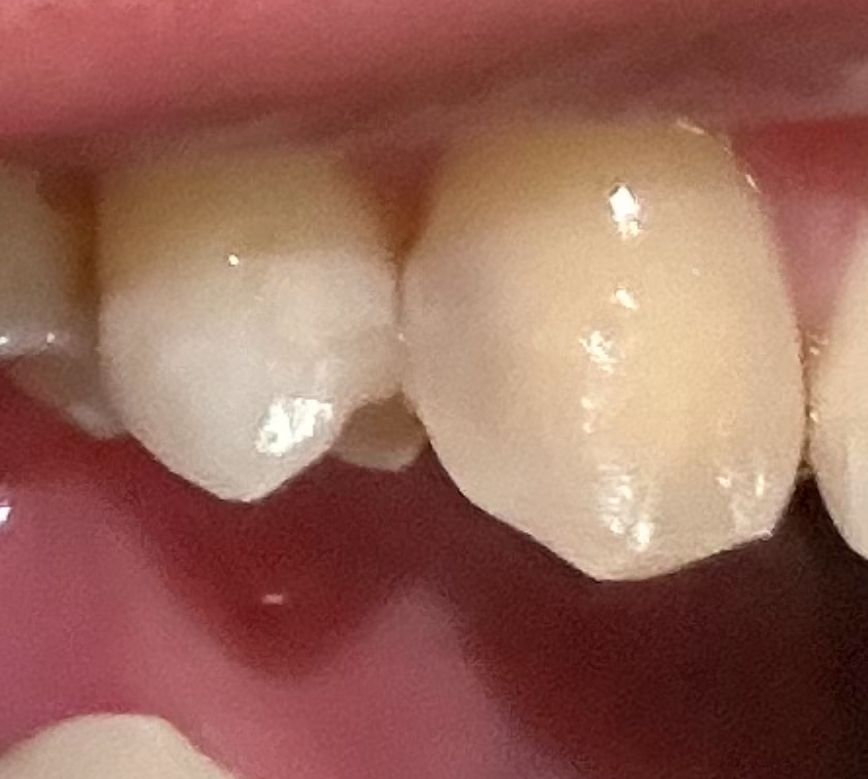

레진 안에 충치가 생긴건가요? 다 같은 송곳니 입니다 마지막 진료는 작년 12월이었습니다

혹시 레진 안에 충치가 생긴건가요? 사진은 다 하나의 송곳니 입니다 핸드폰 라이트를 비추면 검은색이 잘 안보이고 라이트를 끄면 잘보이는 거 같아요

• 2번 째 사진

• 사진으로는 단순히 레진이 투명한 것으로 보이지만 정확한 것은 엑스레이를 찍어봐야 합니다.

걱정되시면 치과 한번 가보시는 게 좋겠습니다.

• 정확한 것은 x-ray 등과 같이 평가해야 합니다. 해당 부분의 레진이 약간 변색되어 나타날 수도 있습니다. 따라서 반드시 검다고 해서 충치가 아니며 빛을 비추는 각도에 따라서 치아 색과 차이가 있다면 조금 더 어두워 보이는 경우도 있으므로 치과 방문 후 검사를 해보셔야 합니다.

• 레진의 색상이나 투명도는 원래 치아와 차이가 있을 수 있습니다 이런 경우 어두워 보이는 경우도 있습니다 크게 문제가 없을 것으로 생각되나 자세한 확인을 위해서는 치과에서 진료를 받아 보는 것을 권유 드립니다

• 사진상으로는 충칭가 확인이 되지는 않습니다. 현재 레진을 한부위가 통증이 있거 해당잇몸이붓는 경우에는 충치가능성이 있기에 치과에 방문하여 상태를 확인인하고 치료를 받길 권합니다.